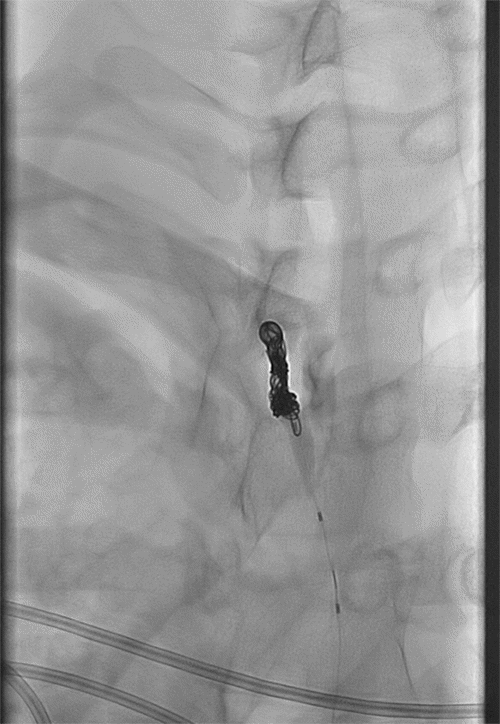

Figure 6. Initial Coil Placement at Defect. Published with Permission

Figure 10. Coil Pack Positioned Within Thoracic Duct. Published with Permission

Glue cast depicting the cisterna chyli